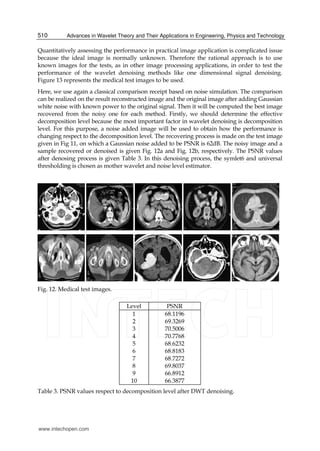

All digital images contain some degree of noise due to the corruption in its acquisition and

Because the wavelet transform has an ability to capture the energy of a signal in few energy

Fig. 11 represents a sample medical image which belongs to a patient having cranial trauma

and its four subimages when decomposed for one level using DWT. This image has acquired

from a BT device. A noise added MRI image and its denoised form using wavelet denoising

procedure is given Fig. 12. The added noise has Gaussian distribution, and symlet6,

Fig. 11. Decomposition of a sample medical image; original, approximation, horizontal